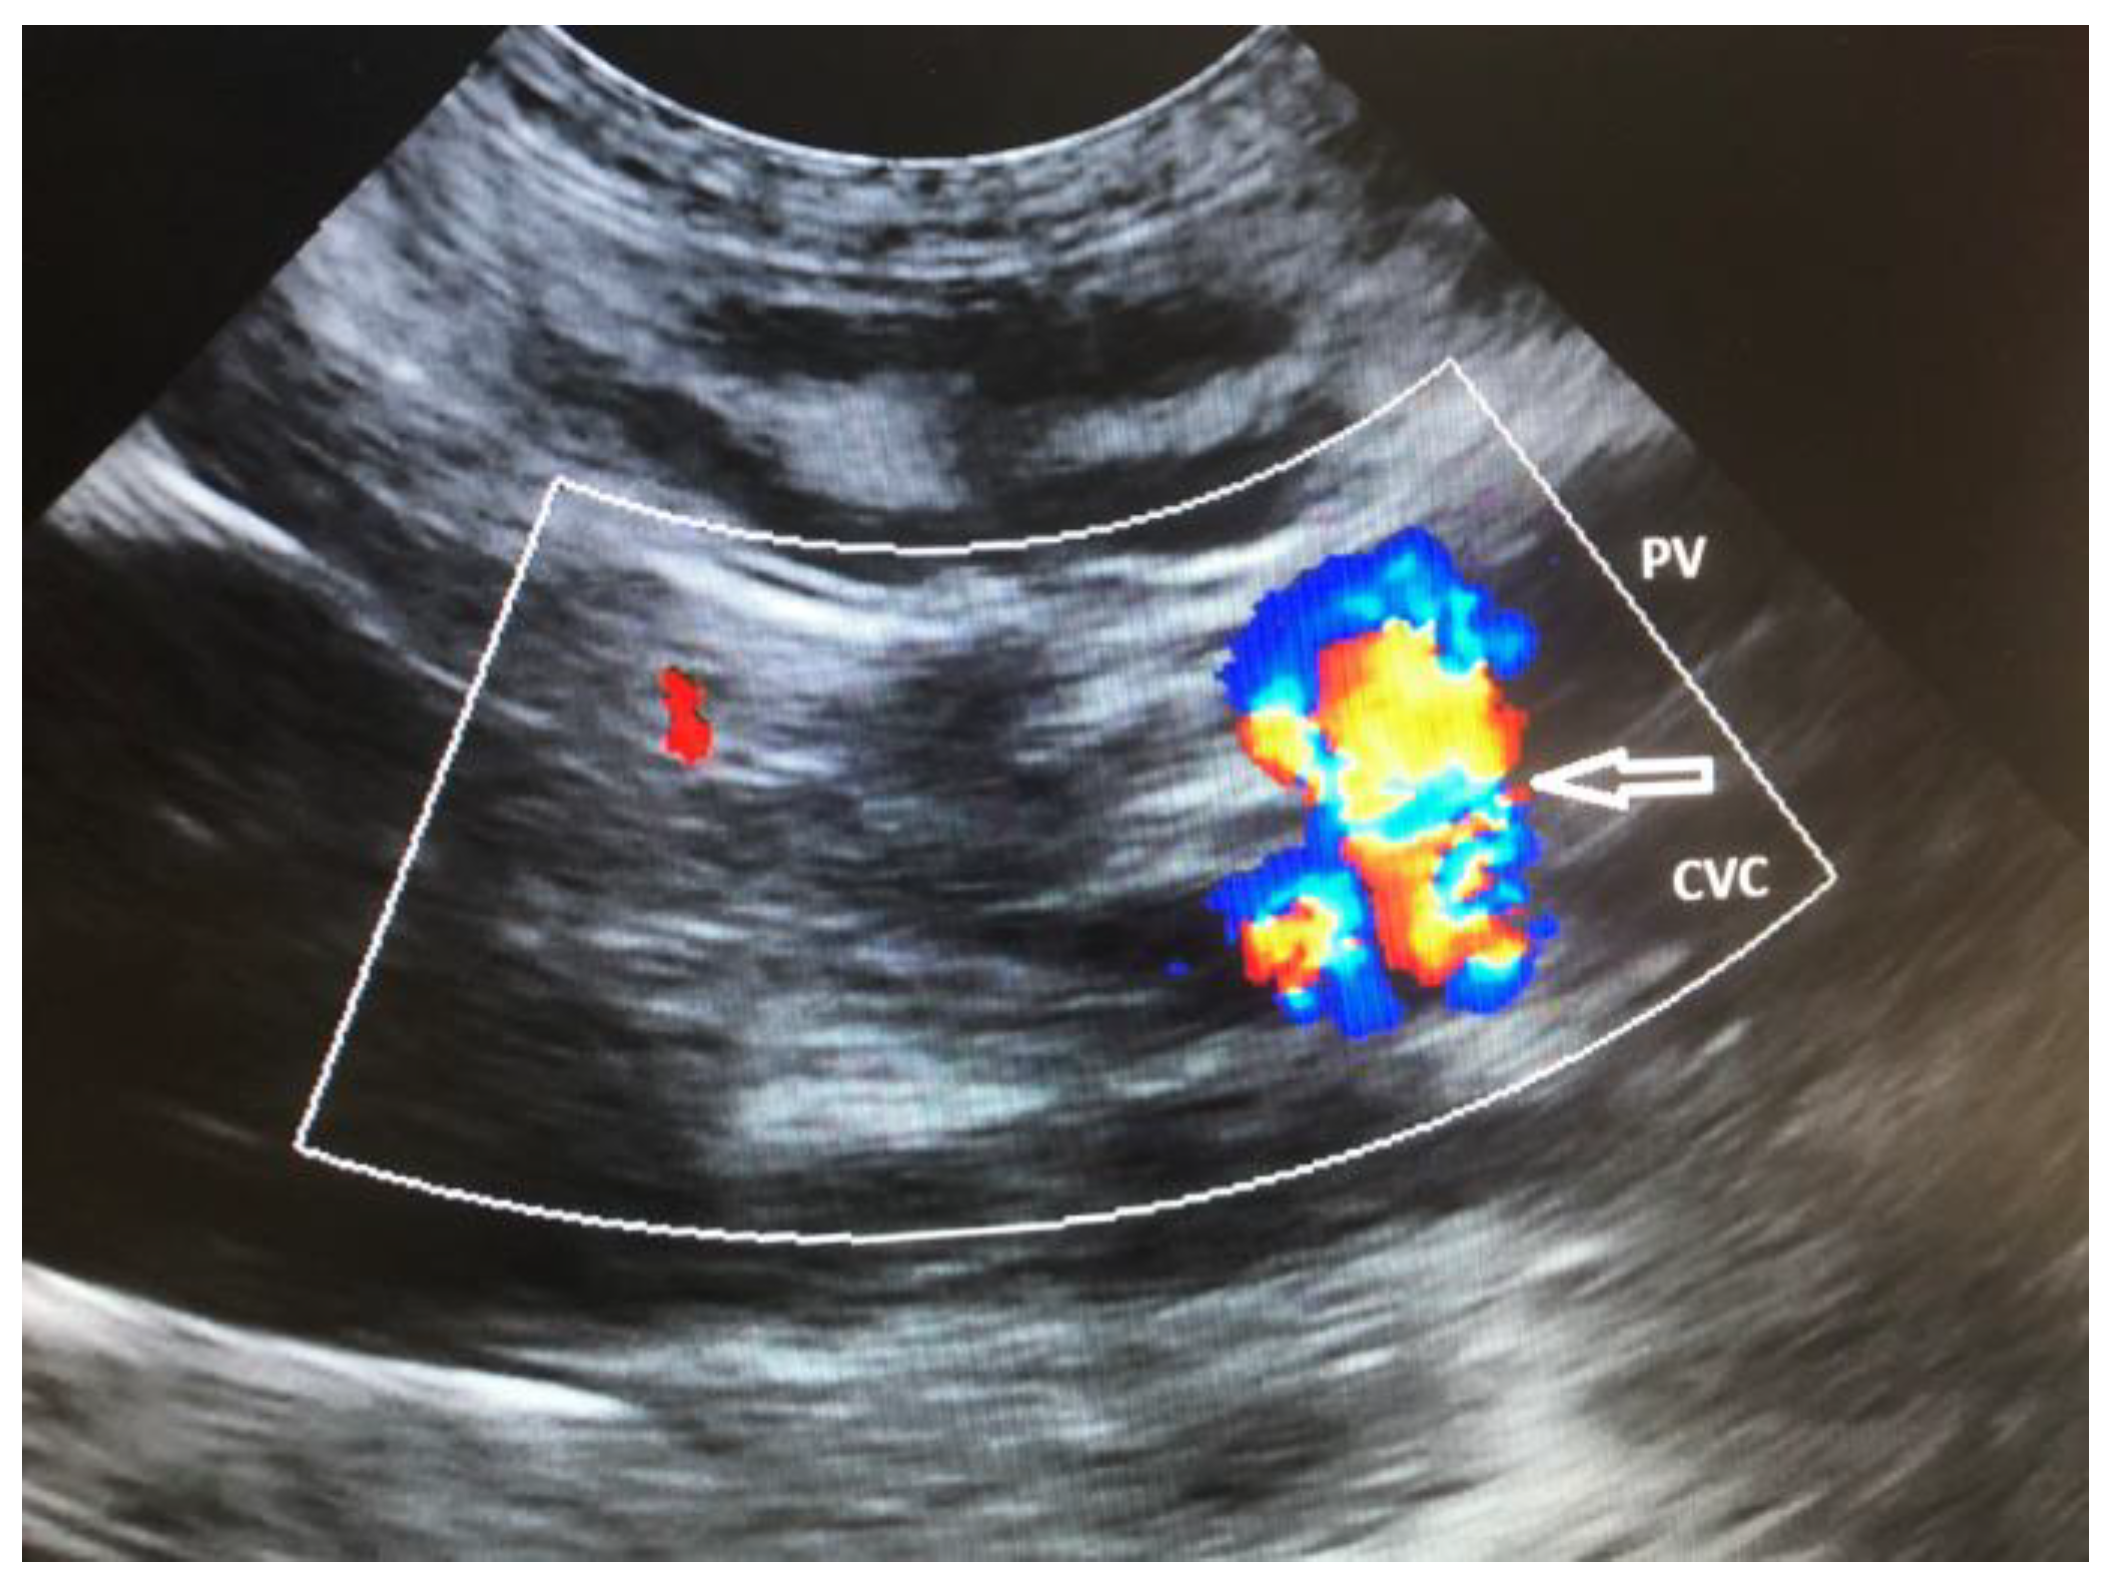

9. Diagnostic Imaging